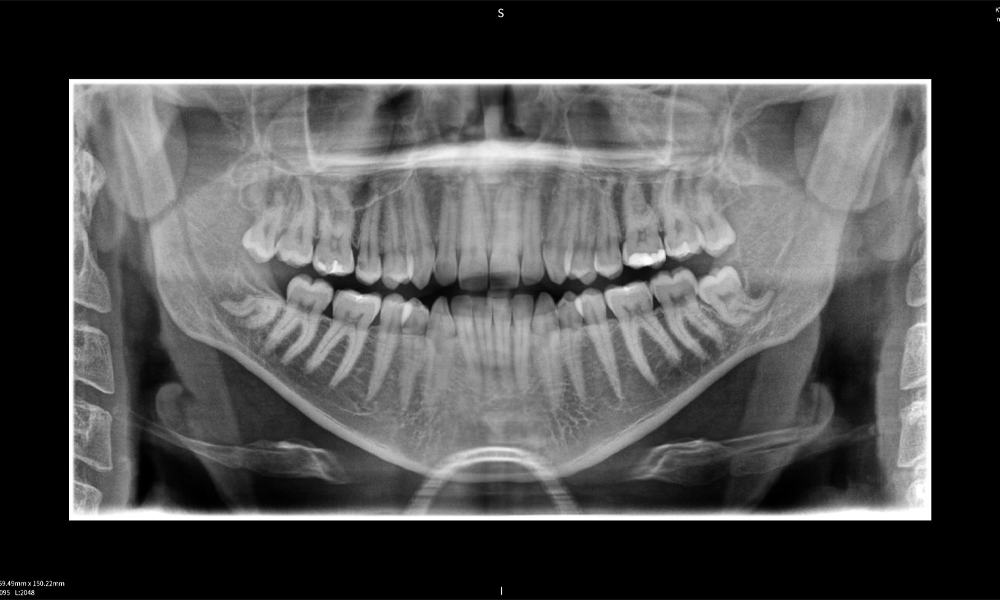

Figura e: La radiografía panorámica sirve como herramienta de evaluación inicial, mostrando la posición general de los dientes, así como posibles cambios patológicos. Es notable que en el lado derecho (diente 48) se observa la situación posterior a una amputación de corona realizada por un profesional externo. Las dos raíces fuertemente curvadas permanecen en estrecha proximidad topográfica al nervio alveolar inferior dentro del hueso. Esto sugiere una decisión deliberada de evitar el mayor riesgo de lesión nerviosa durante una extracción completa y representa un hallazgo clínicamente relevante. En resumen, las tomografías CBCT con Seethrough Max proporcionan información crucial sobre la anatomía compleja y la relación crítica entre las muelas del juicio y el nervio alveolar inferior. Esta imagenología diagnóstica detallada preoperatoria es esencial para realizar procedimientos quirúrgicos seguros y exitosos en la región mandibular.